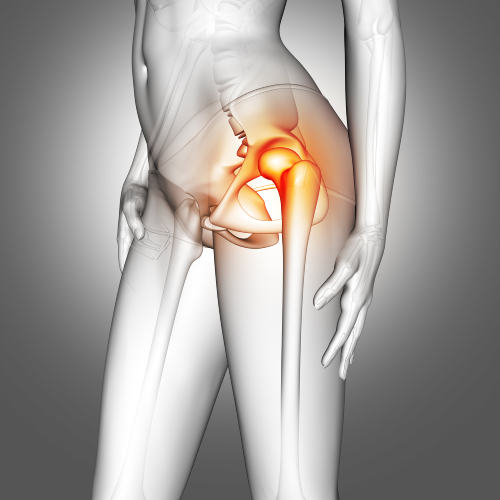

Фото из свободных источников.

Коксартроз (или артроз тазобедренного сустава) — хроническое заболевание, в основе которого лежат дегенеративно-дистрофические процессы, затрагивающие главным образом хрящ, а также другие структуры сустава, в результате чего нарушается опорная и двигательная функция. Данное заболевание без видимой причины возникает у пациентов в возрасте старше 40 лет. У спортсменов после полученных травм (разрывов мениска, связочного аппарата) может развиваться посттравматический коксартроз в молодом возрасте.